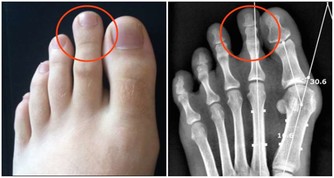

從經絡循行來看,足厥陰肝經起於足大趾外側,沿著下肢內側向上走行,在生殖器環繞一周進入小腹後,直接斜行至兩側腰腹部,行於軀幹外側線。所以,腰部不但是腎的所在,也是肝經走行之處,當肝出現問題,就會擾動腎府,引起腰痛。